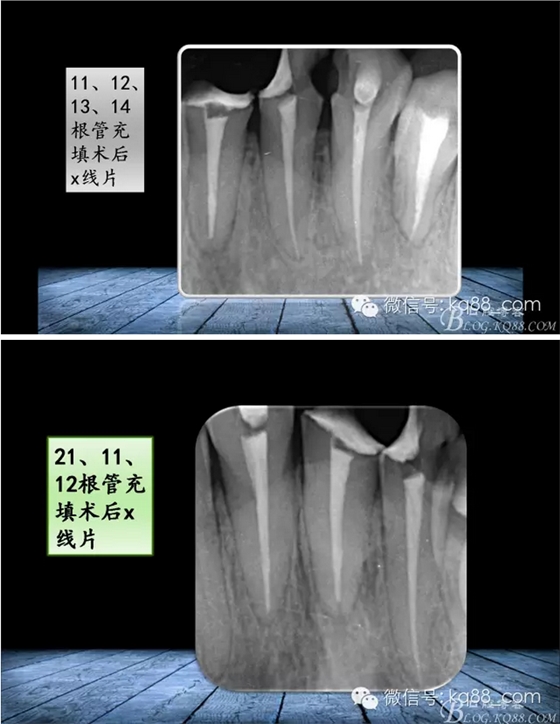

張瑞鋒:簡(jiǎn)單的事情認(rèn)真做——我的根管治療